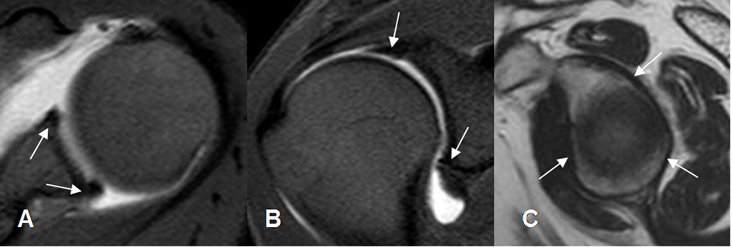

Fig 27. Labrum normal.

A, B, C y D: RM axial en FFE. Distintas configuraciones normales del labrum anterior.

Fig 28. Labrum normal.

A: ArtroRM axial. Rebordes normales anterior y posterior.

B: ArtroRM coronal. Rebordes normales superior e inferior.

C: RM sagital en T2. Labrum adherido a la cavidad glenoidea.

Fig 29. Surco sublabral normal.

ArtroRM coronal. Defecto regular en el labrum superior, que corresponde al surco sublabral.